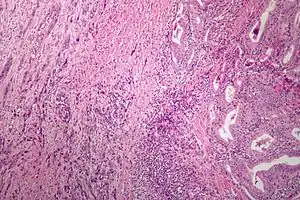

| Microscopic image of anaplastic thyroid carcinoma. H&E stain. | |

Anaplastic tumors have a high mitotic rate and frequently invades the local blood and lymphatic vessels.[5] Cellular death is frequently visualized on microscopic images.[2] The presence of regionally swollen lymph nodes in older patients in whom needle aspiration biopsy reveals characteristic vesicular appearance of the nuclei supports a diagnosis of anaplastic carcinoma. Microscopic images of ATC usually show inflammatory cells from the immune system such as T cells and macrophages.[2]

On immunohistochemistry testing, ATC is usually positive for the keratin, p53, and PAX8 proteins and is negative for thyroid transcription factor-1, thyroglobulin, and calcitonin.[2] ATC cells demonstrate high levels of PD-L1 expression.[2] BRAF and TERT mutations are seen more commonly in ATC than in differentiated thyroid cancer.[2]